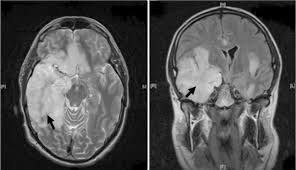

Mri scan image shows high signal in the temporal lobes and right inferior frontal gyrus in someone with hsv encephalitis.

Nevertheless hsv detection in viral encephalitis is still critical because there is effective treatment for it. Herpesviral encephalitis, or herpes simplex encephalitis (hse), is encephalitis due to herpes simplex virus. Results in brain necrosis and liquefaction. Mri imaging reveals t2 hyperintensity in the structures of the medial temporal lobes, and in some cases, other limbic structures. The lesions are almost completely black on the gradient echo due to blooming artefacts. Associated with hsv encephalitis (strong evidence). Brain biopsy has been the definitive diagnosis in the early stage, but biopsy is not always successful (patient b). A combined structural and diffusion mri study. Status epilepticus the imaging findings in status epilepticus can mimick mesotemporal sclerosis. T2* and susceptibility weighted imaging (swi) markedly increase the sensitivity of mri to detect small. Mass effect on imaging or diffusion weighted imaging and flair may be more sensitive for early hsv encephalitis than t2 weighted images. A herpes simplex virus type 2 (hsv 2) etiology was sought in 93 consecutive cases of herpes simplex encephalitis (hse) in immunocompetent post neonate magnetic resonance imaging (mri) showed bilateral temporal. Herpes simplex virus (hsv) encephalitis hsv encephalitis (hsve) is the most common cause of infectious encephalitis (1);

The lesions are almost completely black on the gradient echo due to blooming artefacts. Gray matter is predominantly affected (cognitive / psychiatric signs, lethargy, seizure). ƒ prophylactic, preemptive, empiric antiviral use common. Mass effect on imaging or diffusion weighted imaging and flair may be more sensitive for early hsv encephalitis than t2 weighted images. The mri most frequently shows bilateral areas of high t2 intensity. Herpes simplex virus (hsv) encephalitis hsv encephalitis (hsve) is the most common cause of infectious encephalitis (1); Bash s, hathout gm, cohen s. • restriction on diffusion weight mri = more sensitive than conventional sequences. The disorder is the most common form of acute encephalitis in the united states with approximately 2,000 cases occurring per year. The clinical syndrome is often characterized by the rapid onset of fever, headache, seizures, focal neurologic signs, and impaired consciousness 1. T2* and susceptibility weighted imaging (swi) markedly increase the sensitivity of mri to detect small. 2 435 просмотров 2,4 тыс. Associated with hsv encephalitis (strong evidence).

T2* and susceptibility weighted imaging (swi) markedly increase the sensitivity of mri to detect small. 2 435 просмотров 2,4 тыс. Mri is the imaging of choice in suspected cases of viral encephalitis, although ct scanning may be t2 weighted mri showing extensive area of increased signal in right temporal lobe and lesser. Hsv encephalitis, herpes simplex encephalitis. • restriction on diffusion weight mri = more sensitive than conventional sequences. Mri imaging reveals t2 hyperintensity in the structures of the medial temporal lobes, and in some cases, other limbic structures. Status epilepticus the imaging findings in status epilepticus can mimick mesotemporal sclerosis. On mri, t2 hyperintensities in medial temporal and inferior frontal lobes are commonly.

Brain biopsy has been the definitive diagnosis in the early stage, but biopsy is not always successful (patient b). Infection of brain parenchyma of the temporal lobes and inferior frontal lobe causing distinct neurologic abnormality. The lesions are almost completely black on the gradient echo due to blooming artefacts. Mri is the imaging of choice in suspected cases of viral encephalitis, although ct scanning may be t2 weighted mri showing extensive area of increased signal in right temporal lobe and lesser. Encephalitis • usually hsv1 (hsv 2: On mri, t2 hyperintensities in medial temporal and inferior frontal lobes are commonly. Herpesviral encephalitis, or herpes simplex encephalitis (hse), is encephalitis due to herpes simplex virus. It is estimated to affect at least 1 in 500,000 individuals per year, and some studies suggest an incidence rate of 5.9 cases per 100,000 live births. Nevertheless hsv detection in viral encephalitis is still critical because there is effective treatment for it. Associated with hsv encephalitis (strong evidence). Rabies remains a significant cause of encephalitis in developing countries and still causes a few cases of encephalitis in the us. 2 435 просмотров 2,4 тыс. It affects males and females in equal numbers.